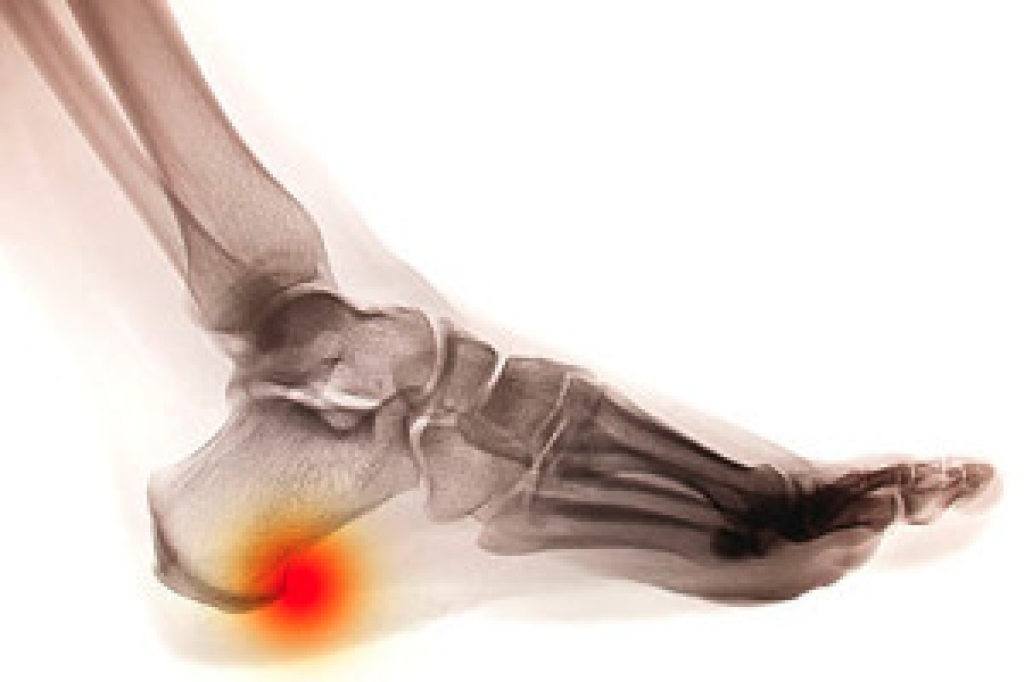

Flip-flops may be the most popular footwear of the summer, but that doesn’t mean that flip-flops are good for your foot health. While they may keep your feet cool, flip-flops can also alter your gait, or walking pattern. When you wear flip-flops, you typically need to scrunch up your toes around the ends of the shoes in order to keep them on. This can stretch the plantar fascia ligament that runs along the bottom of the foot and lead to heel and arch pain and plantar fasciitis. Another thing you might be doing to keep those flip-flops on your feet is walk with shorter strides and turn your ankles inward while you walk. This altered gait can cause long term ankle and hip problems. This summer, if you must wear flip-flops, choose ones made of a sturdier material and wear them infrequently. For more information about the effects of footwear on your feet, please consult with a podiatrist.

- Problems with foot arches

Yes. Since flip-flops are relatively weak and do not provide the same amount of support as sneakers, people who wear flip-flops regularly are more susceptible to injuries. On top of that, the open nature of the shoe makes your feet more prone to other problems, such as cuts and even infections. Common injuries and ailments include: